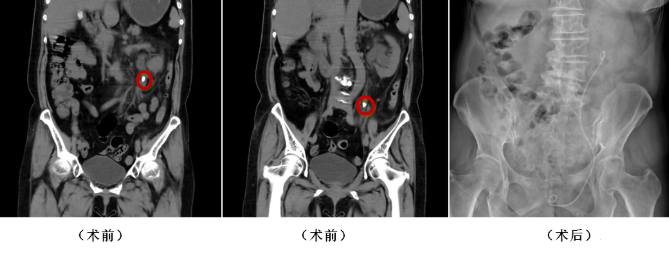

患者張先生(化名)左側(cè)腰腹部疼痛20余天,檢查提示左側(cè)輸尿管盆段結(jié)石伴腎積水、感染,同時合并高血壓、前列腺增生、頸動脈斑塊等多種基礎(chǔ)疾病,手術(shù)風(fēng)險更高。張寶主任團(tuán)隊術(shù)前全面評估患者心肺功能及基礎(chǔ)疾病,制定個性化麻醉與手術(shù)方案,在全麻下為其實施經(jīng)尿道輸尿管鏡激光碎石術(shù),高效清除結(jié)石后留置支架管。術(shù)后通過抗感染、補液、解痙止痛等對癥治療,患者病情平穩(wěn),自主排尿恢復(fù)良好,各項指標(biāo)逐步回歸正常,順利出院。